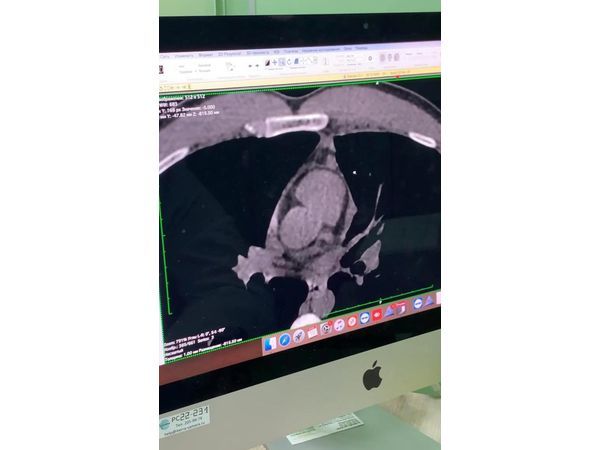

- компьютерную топографию органов грудной клетки (КТ ОГК) — обнаружено объёмное образование средостения;

Лимфома Ходжкина.